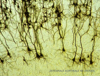

Der Gesundheit des Gehirns wird wenig Aufmerksamkeit geschenkt, bis die Besitzer neurologische oder Verhaltensprobleme bei ihren Haustieren bemerken. Wenn diese Veränderungen bemerkt werden, können bereits potenziell irreversible Schäden am Gehirn entstanden sein. Aber was wäre, wenn wir früher eingreifen könnten?

Die Forschung von Purina hat zu Innovationen in der Fütterung geführt, die Tierärzten helfen können, die Gesundheit des Gehirns zu schützen, altersbedingte kognitive Veränderungen bei Hunden und Katzen zu bewältigen und die Ergebnisse im Zusammenhang mit idiopathischer Epilepsie bei Hunden zu verbessern. Nur 2 % der Tierärzte sind sich des Zusammenhangs zwischen der Gesundheit des Gehirns und der Ernährung bewusst.1 Ein größeres Wissen und Verständnis ist eine Gelegenheit, proaktivere Gespräche mit den Besitzern älterer Haustiere zu führen.